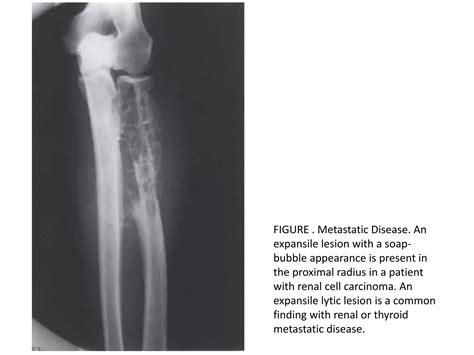

• Metastatic Carcinoma: Breast, lung, and renal cell carcinomas are common sources of bone metastases that appear lytic.

Metastatic Disease Ill-defined, permeative lesions Patients with known primary cancer

Unicameral Bone Cyst Geographic lesion, expansile Children/Adolescents